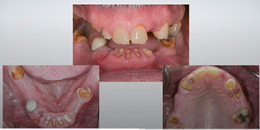

Figure 14 through Figure 18 show a partially dentate patient for whom a fully digital workflow was utilized. This 47-year-old male presented with root blunting and mobility of teeth Nos. 7, 8, and 9 (Figure 14). A thermoplastic clip was attached during the CBCT, and an intraoral scan was taken and superimposed on the CBCT. The case was then planned in the navigation planning software (Figure 15). Once the teeth were extracted, intraoral scanning was performed. The intraoral scan was imported into lab software (Figure 16), and a PMMA milled screw-retained prosthesis was fabricated. The prosthesis was placed the next morning (Figure 17). Two months later, a new intraoral scan was taken to capture the mature soft tissue, and the final milled titanium abutment and restoration were delivered (Figure 18).

Fig 14. Preoperative view of a partially dentate case. Patient with root blunting and grade 3 mobility.

Figure 14

Fig 15. The case was planned using navigation planning software in this same patient.

Figure 15

Fig 16. Virtual design of the provisional prosthesis.

Figure 16

Fig 17. Views of the milled PMMA screw-retained provisional restoration. Note the screw access holes in the incisor edges (left panel). (Images courtesy of Dr. Kim Knoll.)

Figure 17

Fig 18. Placement of the final prosthesis. Milled titanium abutments (left panel) and Emax crowns (right panel). (Images courtesy of Dr. Kim Knoll.)

Figure 18